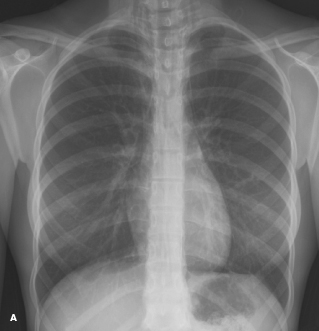

spontaneous pneumomediastinum

Lisa M. Clewner, MD